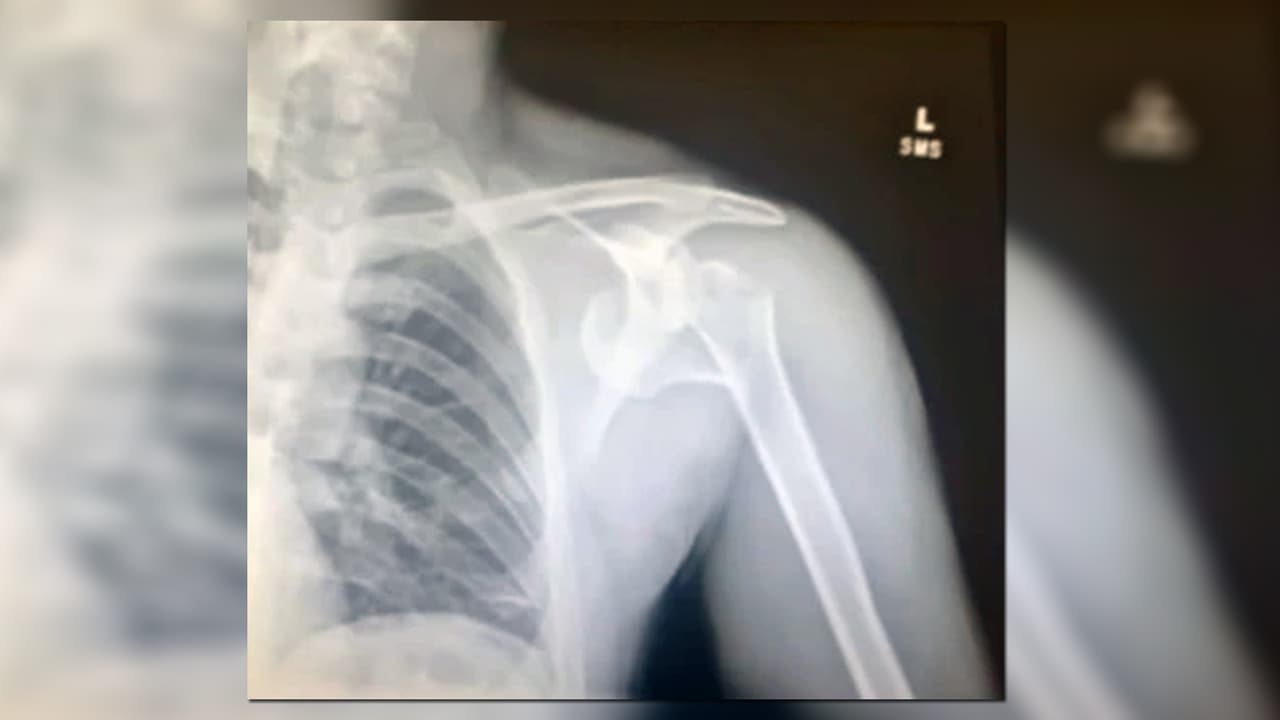

Tenía un fuerte golpe en la cabeza, sus dientes rotos y heridas en su pierna y hombro izquierdo. Además, le habían robado su teléfono y una tarjeta de crédito.

Producto de la violenta experiencia, Dustan Jackson confesó que tiene problemas nerviosos y lo han operado varias veces para reconstruir su hombro.